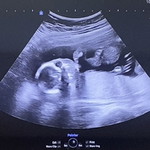

อยากสอบถามแม่ๆ ตรวจนิฟกันไหมคะ จำเป็นต้องตรวจไหมคะ ตอนนี้ 22 w. แต่คุณหมอบอกไม่มีพาหะความเสี่ยงอะไรเลย หรือควรไปตรวจดีคะแม่ๆ ขอบคุณค่ะ❤️ #ท้องแรก #ลูกคนแรก #ขอบคณสำหรับคำตอบล่วงหน้านะคะ

ส่วนตัวบ้านนี้ตรวจตั้งแต่ 14 week ค่ะ อยากได้ความชัวร์มากว่าการซาวด์ค่ะ เพราะการซาวด์ไม่สามารถบอกถึงความผิดปกติได้ 100% เลยเลือกที่จะตรวจนิฟค่ะ แต่ไม่แน่ใจของคุณแม่ตอนนี้ 22 week แล้วยังจะทันรึป่าวนะคะ

22w ไม่ทันแล้วค่ะ ถ้าเกิดเสี่ยงก็เอาออกไม่ได้แล้วค่ะ ถ้าคุณหมอไม่ทักอะไร ก็น่าจไม่มีอะไรนะคะ

22W ตรวจนิฟไม่ทันแล้วค่ะแม่